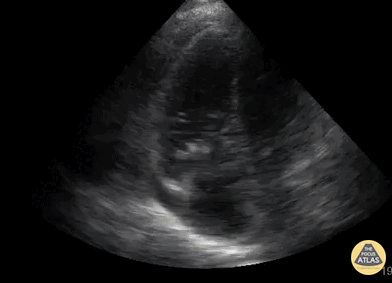

56 yoM with pmh of many things including COPD and E. fecalis endocarditis of AV, MV, TV s/p TV vegetation debulking and angiovac who presented with COVID hypoxia and meeting SIRS criteria, ended up having E. fecalis bacteremia and was transferred to Bellevue for further vegetation debulking and tx of endocarditis. We did bedside echo which showed the TV vegetations and chronic RVH and right heart strain. Jamie POSPISHIL